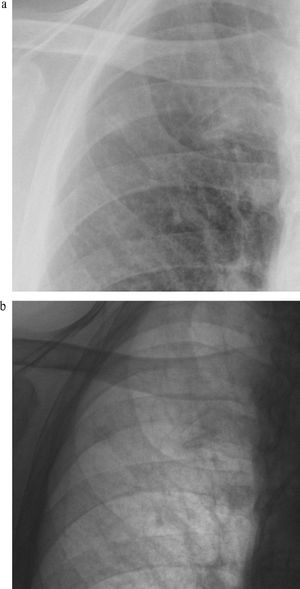

Study identifies lowest possible radiation dose that still allows for detection of pleural effusions, thickening and calcification.